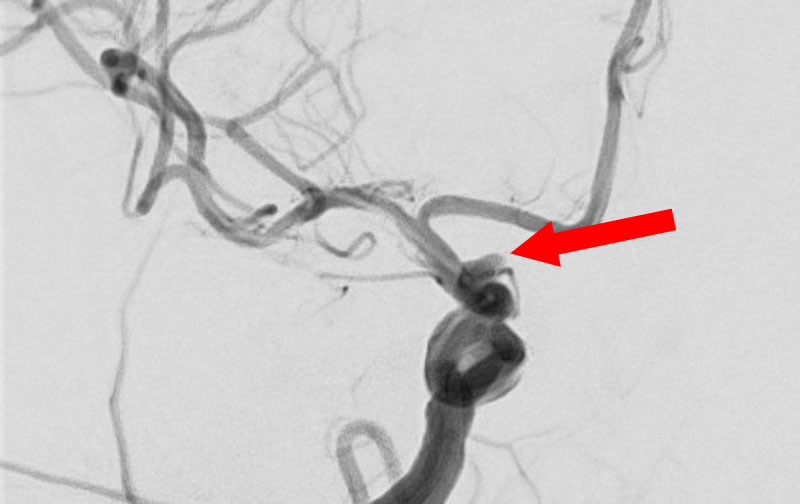

No.1631 手術後